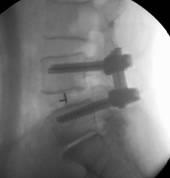

近日,市四医院脊柱创伤外科手术团队在全市较早将微创经椎间孔腰椎椎体融合技术(misTLIF)用于腰椎管狭窄症和腰椎滑脱症患者。手术为经皮微创置钉,在通道下行神经减压椎体复位及椎间融合,手术切口仅有几厘米,手术创伤小,患者术后次日可下床。完成该手术的两名患者腰腿痛症状缓解,手术取得明显成效。

misTLIF手术是近年来发展起来的一项骨科新技术,主要用于腰椎管狭窄症、腰椎滑脱症。它与传统的开放手术相比,有着明显优势,术中切口小,创伤出血少,且无需广泛切开肌肉韧带等软组织,避免了因肌肉软组织剥离过多而导致的迟发性脊柱不稳;由于手术创伤小,术后患者恢复快,可以尽早下床活动,减少了术后切口感染以及卧床时间过长带来的一系列并发症。